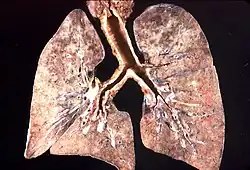

Pneumocystoza (łac. pneumocystosis, PCP) – zapalenie płuc wywołane przez grzyba Pneumocystis jiroveci (dawna nazwa Pneumocystis carini, który był klasyfikowany jako pierwotniak), u osób z zaburzeniami odporności komórkowej[1]. Do zakażeń dochodzi drogą wziewną, u chorych na AIDS, białaczki, chłoniaki lub leczonych immunosupresyjnie.

Choroba wywoływana jest przez oportunistyczny pasożytniczy grzyb Pneumocystis jiroveci. Do zarażenia dochodzi przez inhalację cyst pasożyta.